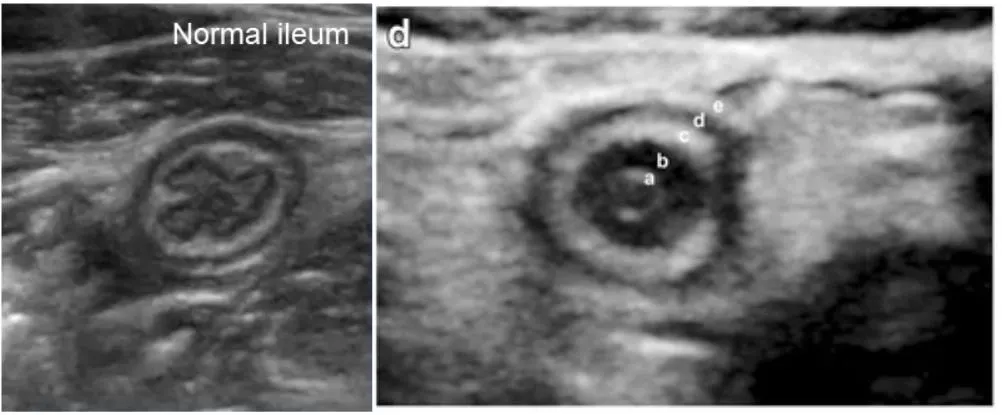

Ileum과 차이점 : Appendix는 inner hypoechogenic mucosa에 fold가 없음.

Appendix는 mucosa가 왜 두꺼운가 - lymphoid tissue 때문

Maximal outer diameter : Maximal mural thickness

Muscularis layer에서부터 반대편 muscularis layer까지 잰다

Threshold : 6mm (민감도는 높으나, 특이도는 낮다)